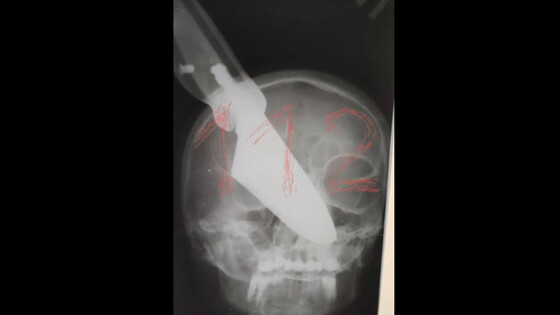

В городе Апшеронске Краснодарского края в ходе семейной ссоры мужчина воткнул нож в лицо своей супруги - женщина осталась жива, сообщается на сайте Следственного комитета по Кубани. Инцидент произошел вечером 19 ноября, когда 64-летний мужчина и 60-летняя женщина распивали спиртные напитки, находясь у себя дома. В ходе ссоры мужчина схватил нож и ударил свою жену ножом в область носа. Клинок застрял в лице женщины, которая сумела отбиться от мужа и выбежать на улицу, где позвала на помощь. "Местные жители вызвали на место бригаду скорой медицинской помощи и правоохранителей. Пострадавшая была доставлена в больницу, где ей продолжают оказывать медицинскую помощь", - указано в сообщении. Мужчина был задержан, ему предъявлено обвинение по ч. 3 статьи 30 и ч. 1 статьи 105 УК РФ в покушении на убийство. Ранее в Подмосковье пьяный сотрудник ГИБДД выстрелил в свою дочь в такси и сбежал.